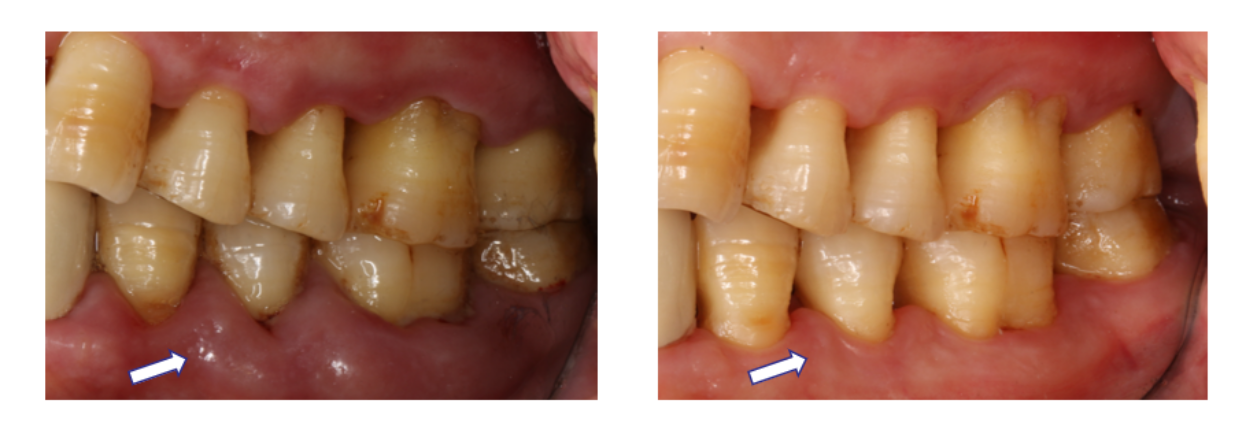

图:治疗前(左)治疗后(右)

完成刮治后,马大叔牙龈的颜色、形态和质地都变得更加健康,不再像“松软的肉袋子”,更有利于清洁,炎症也得到有效抑制。X光片证明他接受牙周基础治疗后,牙槽骨情况也得到很大改善。

马大叔表示,口腔比以前感觉更清爽,异味少很多,现在配合吃药治疗,血压比以前稳定,不再动不动就住院了。